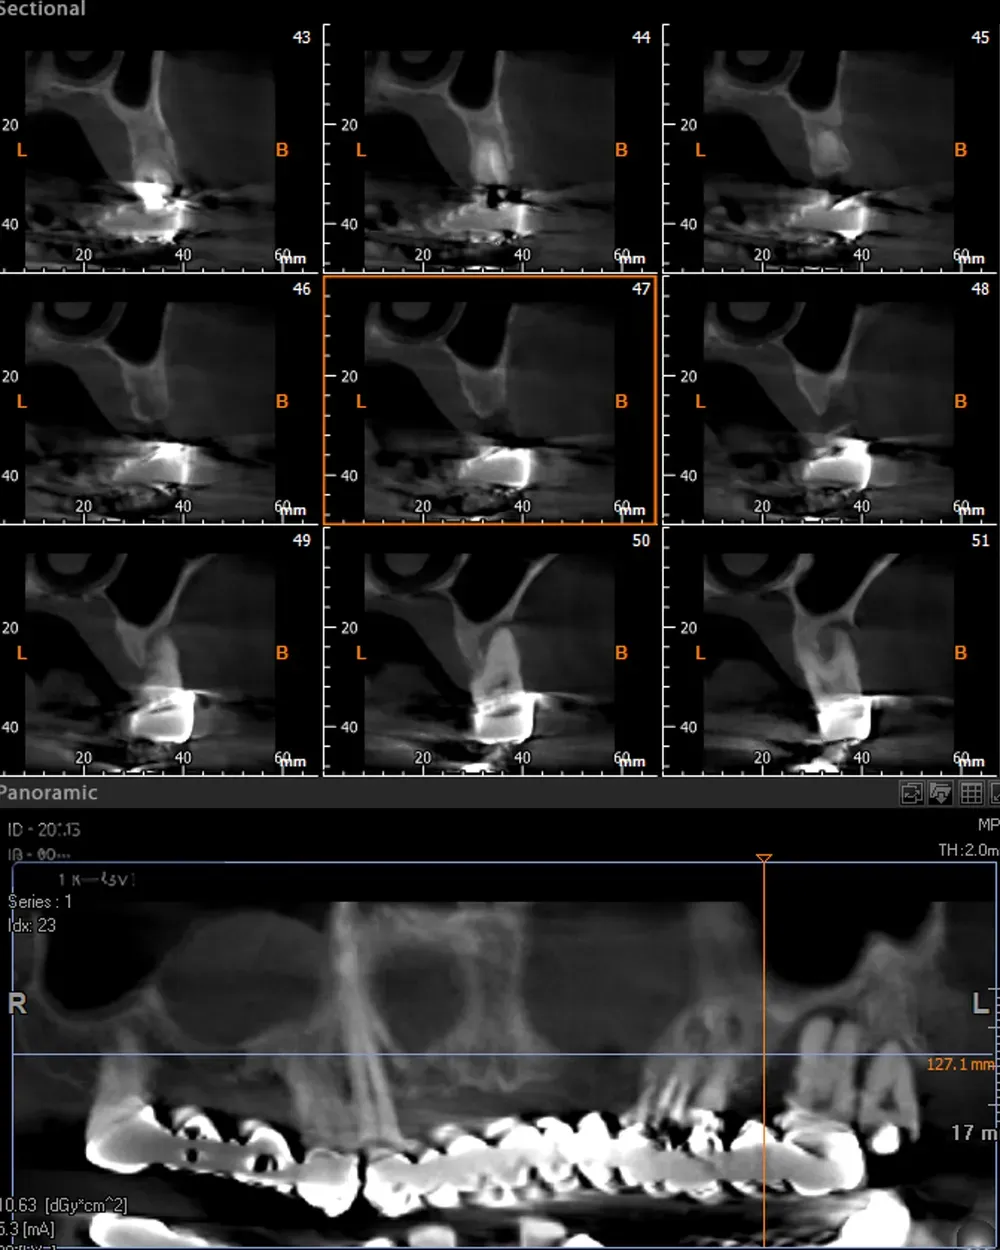

Le immagini sottostanti illustrano la situazione ossea pre-operatoria della cresta alveolare, con una grave atrofia orizzontale, corrispondente alla categoria H3 della Classificazione di Colonia (CCARD).

Secondo la BDIZ EDI, tale grado di atrofia controindica le tecniche espansive.

Personalmente, tuttavia, ritengo che con gli strumenti moderni sia possibile e consigliabile spingersi oltre per includere anche tale livello di atrofia tra le indicazioni. E questo caso lo dimostra.

Sul lato sinistro, l’atrofia dopo la rimozione dei denti e la rigenerazione era comunque meno grave e rientrava nell’ambito delle categorie S1-S2 CCARD. La prossima immagine è la CBCT della zona mascellare sinistra prima delle estrazioni.